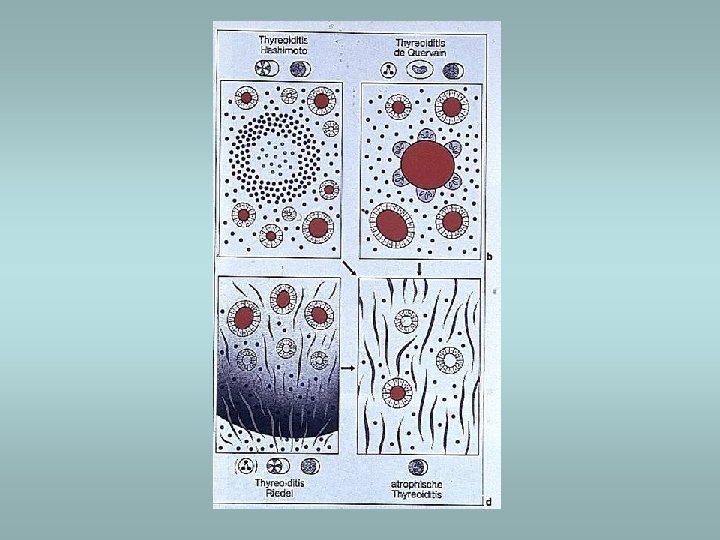

Thyroiditis ü ü ü Hashimoto’s thyroiditis De Quervain’s thyroiditis Riedel’s fibrosing thyroiditis Lymphocytic thyroiditis Infectious thyroiditis

Hashimoto’s thyroiditis ü Autoimmune disorder ü Female predominance ü Defect in suppressor T cells, production of autoantibodies ü Associated with other autoimmune disease (SLE, Sjögren sy, rheumatoid arthritis…) ü Microscopically – dense lymphocytic infiltrate, germinal centers, abundant eosinophilic oncocytes (Hürtle cells)

De Quervain’s subacute granulomatous thyroiditis ü Also known as giant cell thyroiditis ü Probably viral etiology ü Destruction of follicles, neutrophil infiltrate, multinucleate giant cells ü Recovery in 6 -8 weeks

Subacute lymphocytic thyroiditis ü Nonspecific lymphoid infiltration ü Without germinal centre ü In women in postpartum period

Riedel’s fibrosing thyroiditis ü Thyroid replaced by fibrous tissue ü Fibrous tissue extends and penetrate into the surrounding neck structures ü May be mistaken for infiltrating neoplasm